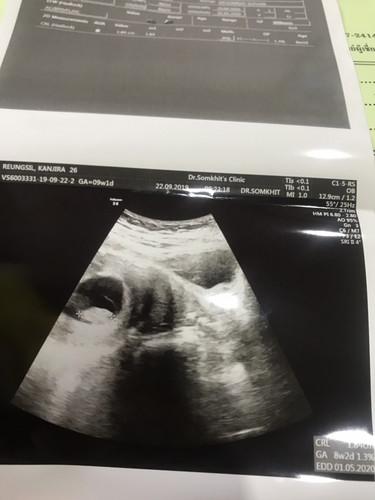

อัลตราซาวด์

มีแม่ๆคนไหนอัลตราซาวด์ตอน 2 เดือนบ้างมั้ยคะ ขอดูหน่อยค่ะ เพิ่งไปฝากครรภ์มาวันนี้ค่ะ

8w5d ค่ะ ตอนนี้คลอดแล้วน้อง 11วันค่ะ